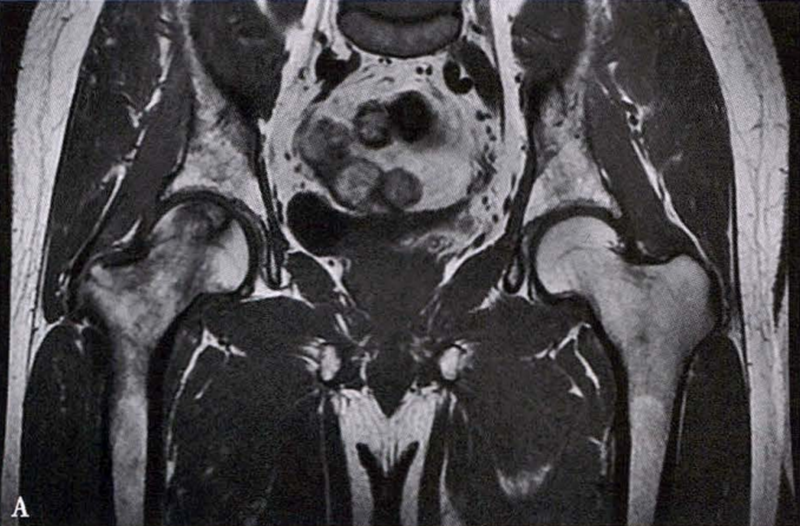

冠状面及横断面MRI图像

MRI示双侧股骨头坏死,冠状面显示右侧股骨头坏死(图A、C),横断面显示双侧股骨头坏死(图B、D);T1加权像(图A、B)显示硬化带为低信号,T2加权像(图C、D)显示右侧骨坏死硬化带外围高信号的骨髓水肿,左侧无骨髓水肿。